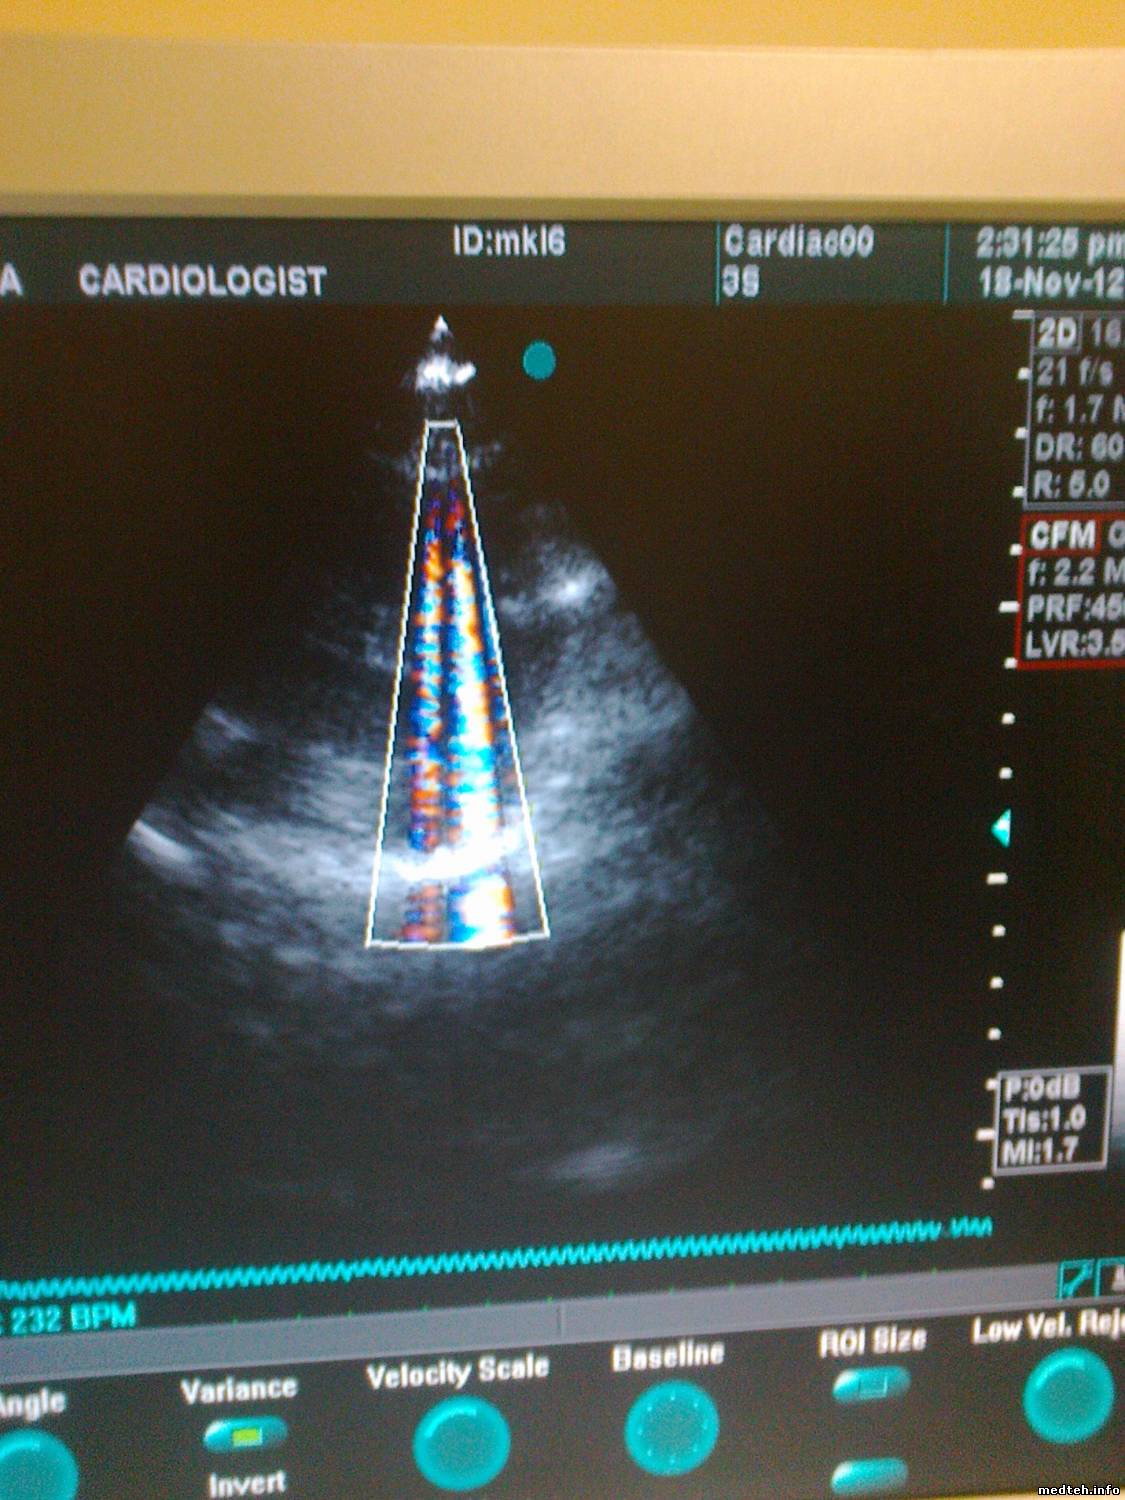

на цветном изображении возникают помехи(см.фото)если у кого-то была такая проблема-поделитесь.

Я склоняюсь больше всего к BF board илт RCT board

1511944.jpg (193.1 Kb) · 5271163.jpg (176.9 Kb)

Судя по фоткам, первоначально я бы уделил внимание датчику, наличию (отсутствию) земли, и качеству питающей сети.

я пробовал другой датчик(с другого рабочего vivid3) и проблема была таже.

На счёт качества сети-аппарат имеет ON-LINE UPS.я пробовал аппарат и от других розеток-проблема таже.